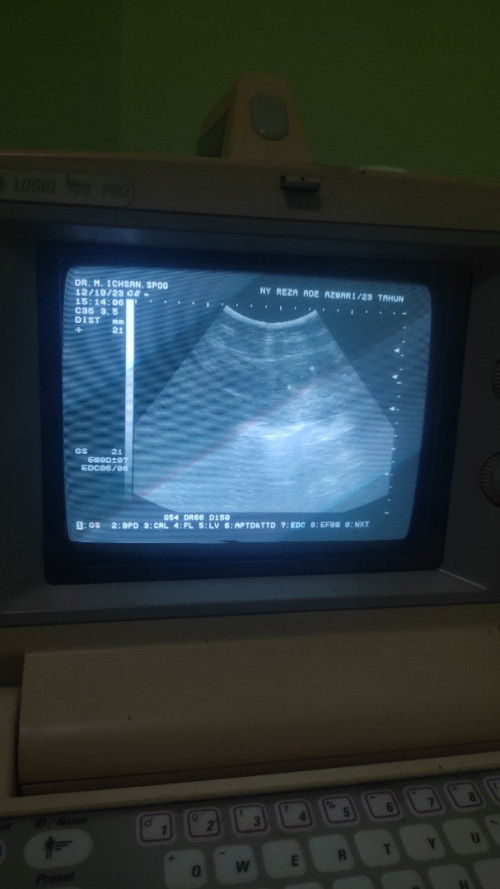

sedang mengandung